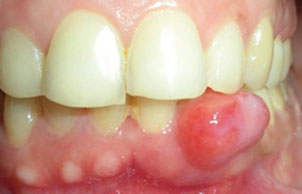

Mucocele

MC lesion of the salivary glands, usually found on bottom lip as a results of trauma, and may have a bluish tinge to them

- can be caused by a blockage or rupture in the ducts

Micro: have cystic spaces filled c mucin and lined by inflam cells

Tx: Complete surgical excision (will recur if not completely excised)

Ranula - mucocele of the sublingual glands

- may grow into a "plunging ranula" - a cyst so large it busts through muscle tissue of the jaw

Mucus escape phenomenon, a pseudocyst from disruption of minor salivary glands, M=F, usually teens to early 20s, Mc on lower lip then bucal

Ranula = sublingual mucocele simple and plunging types

Histo: no true cyst wall, histiocytic response to mucus